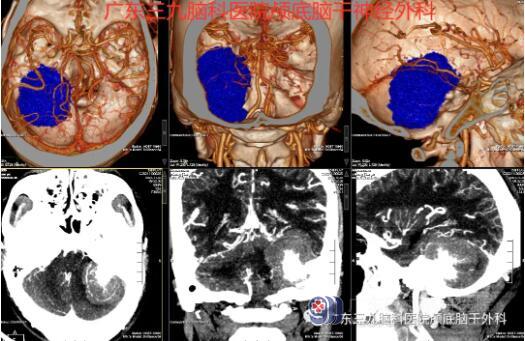

“患者脑膜瘤的位置在后颅窝左侧跨小脑幕上下,大小约49×48×49mm,此部位的脑膜瘤很常见,大部分质地软,容易切除。少部分质地硬,切除困难。”神经外一科主任张良介绍说。

针对患者的病情,神经外一科在科室主任张良的带领下,对患者的身体情况进行全面的术前讨论,制定了详细的手术方案,做好了充分的术前准备。与患者家属充分沟通后,于129号在全麻下行“左侧桥小脑角区脑膜瘤切除术”,术中注意保护后组神经、三叉神经和面瘫神经。整个术程顺利,病理报告示: (右侧桥小脑角)纤维型脑膜瘤,CNSWHO I级。